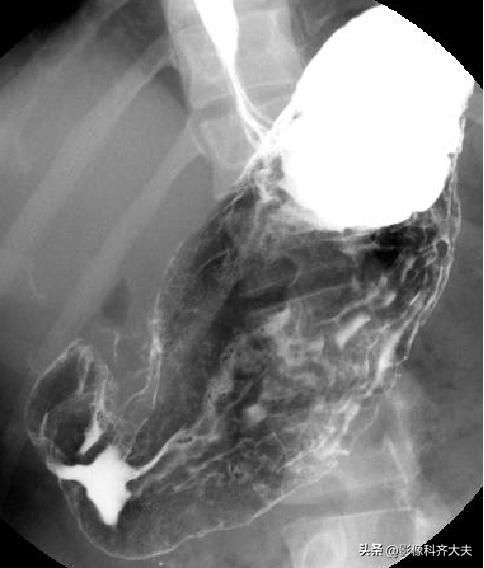

胃底、贲门双对比相(右前斜位)

胃底、贲门双对比相(左前斜位)